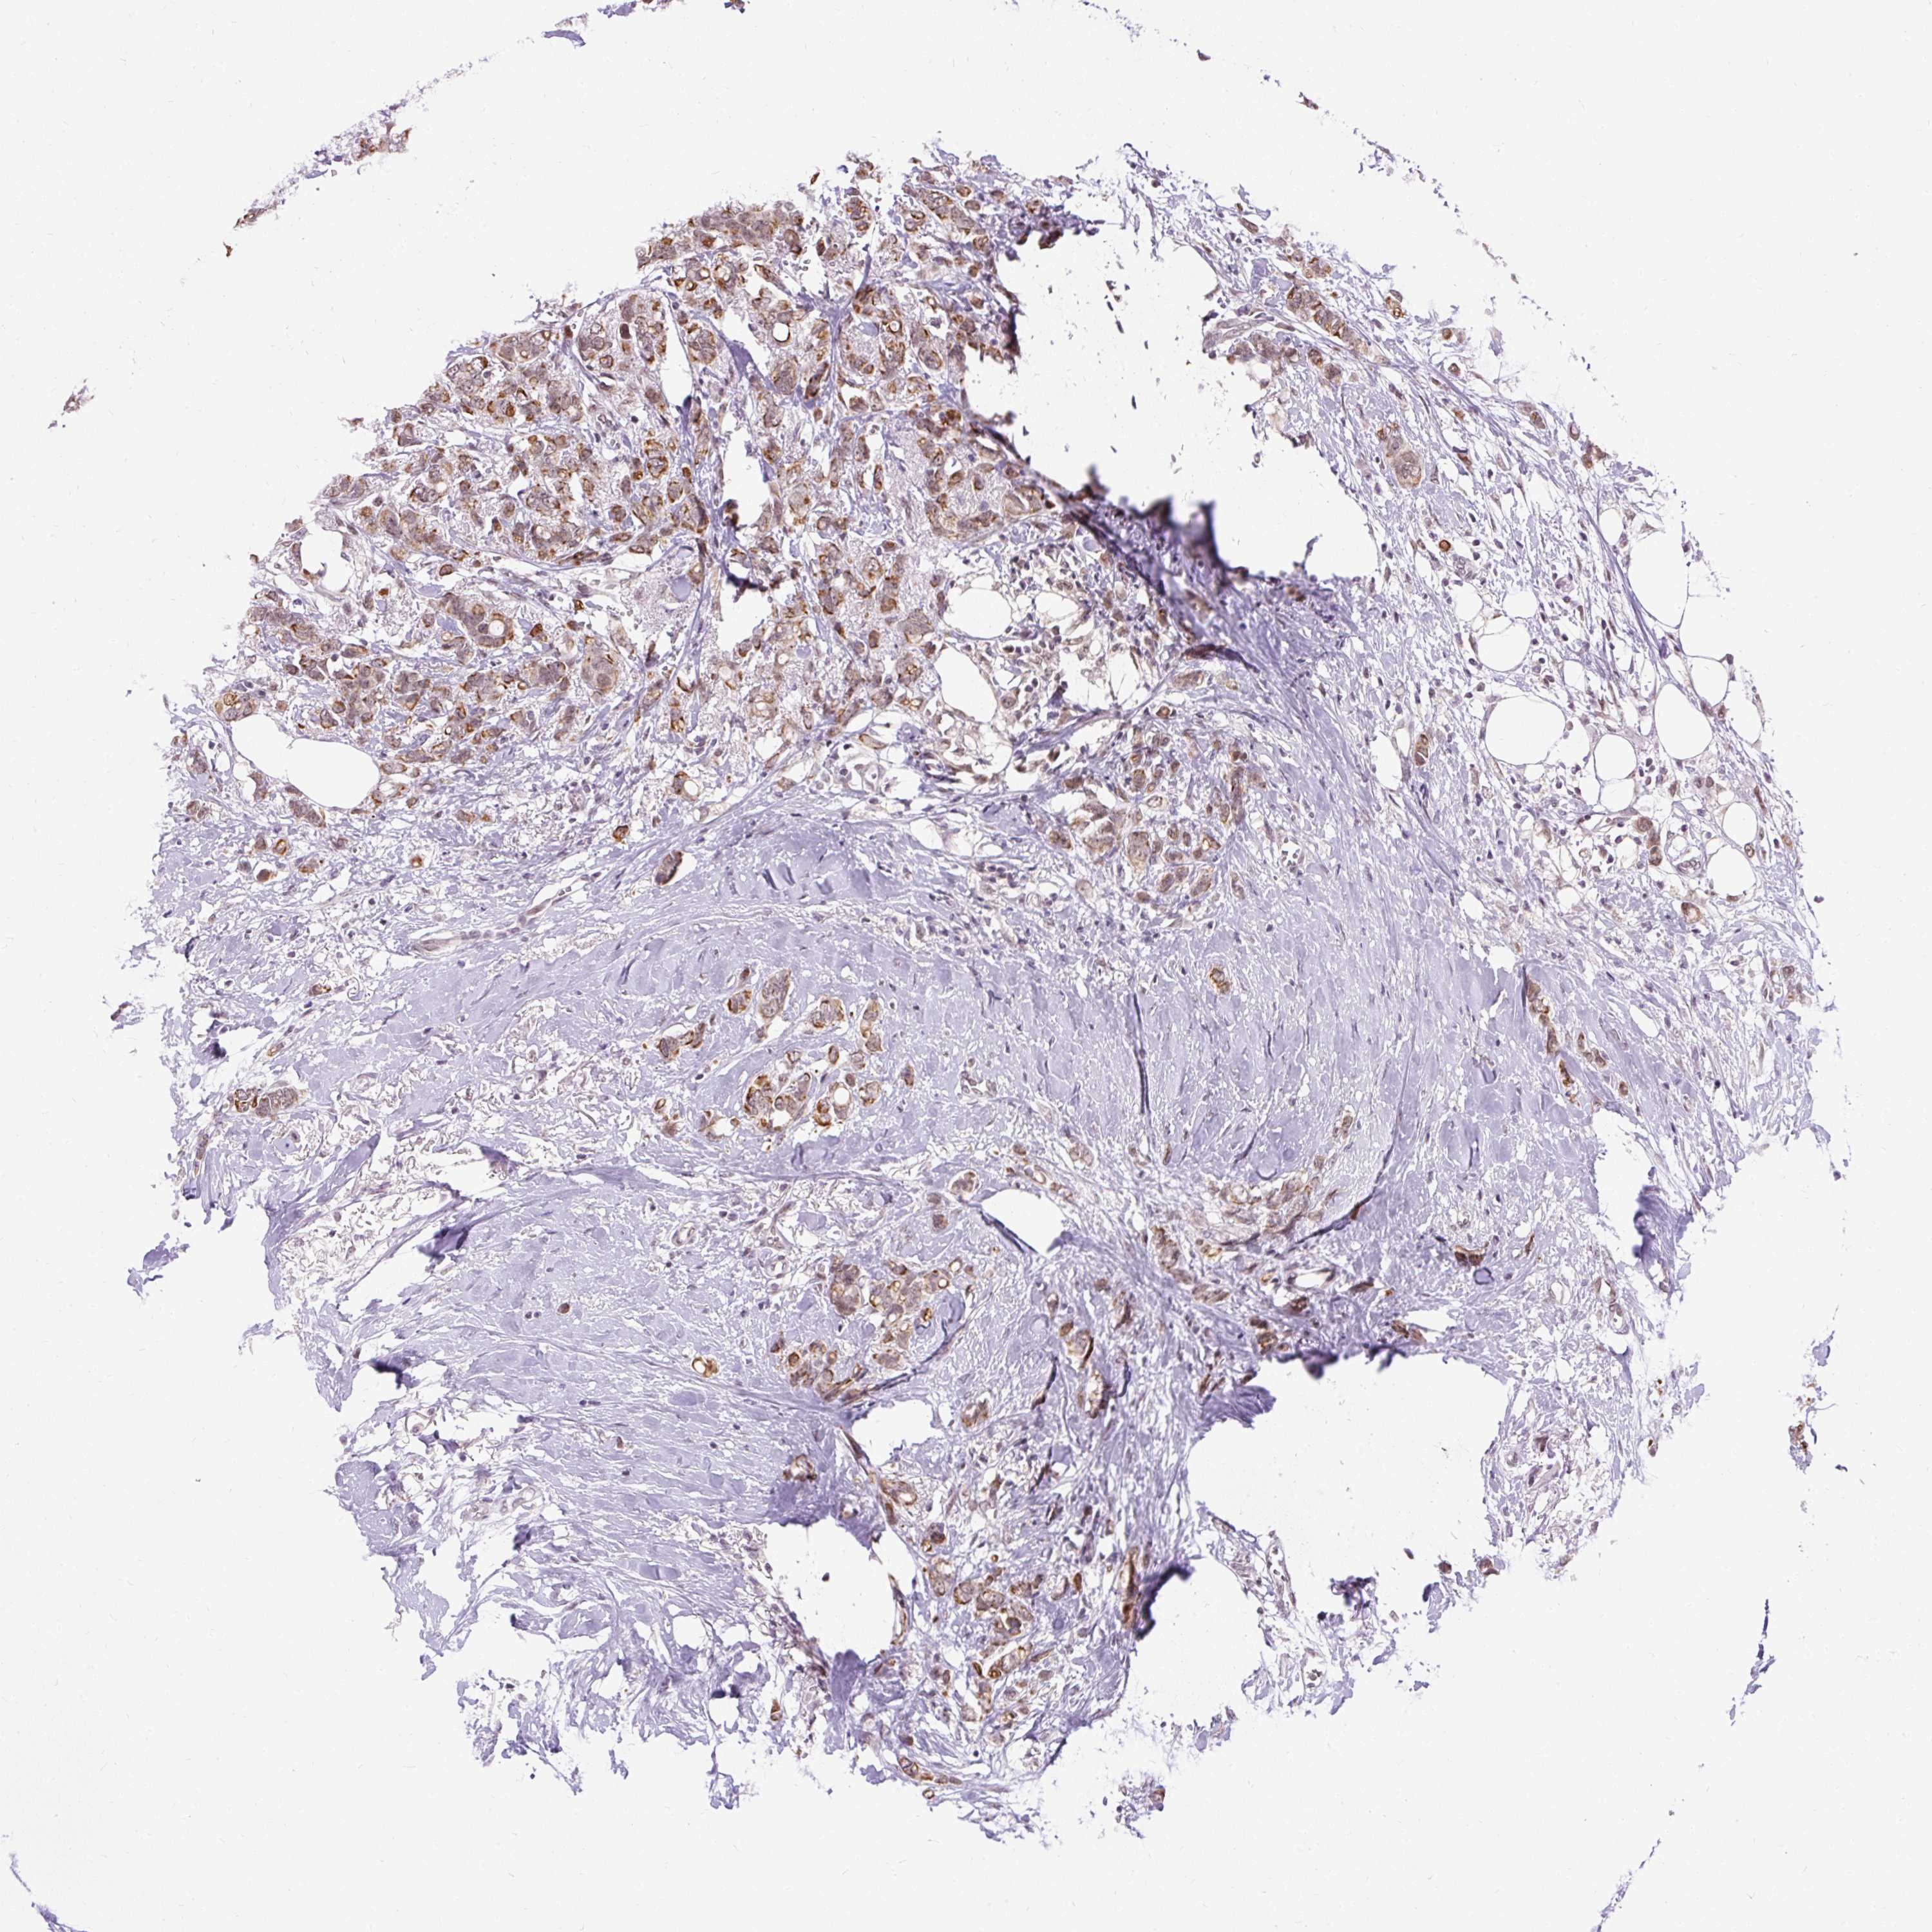

CANCER BREAST CANCER Show tissue menu

BRCA TCGA BRCA VALIDATION PROTEIN EXPRESSION